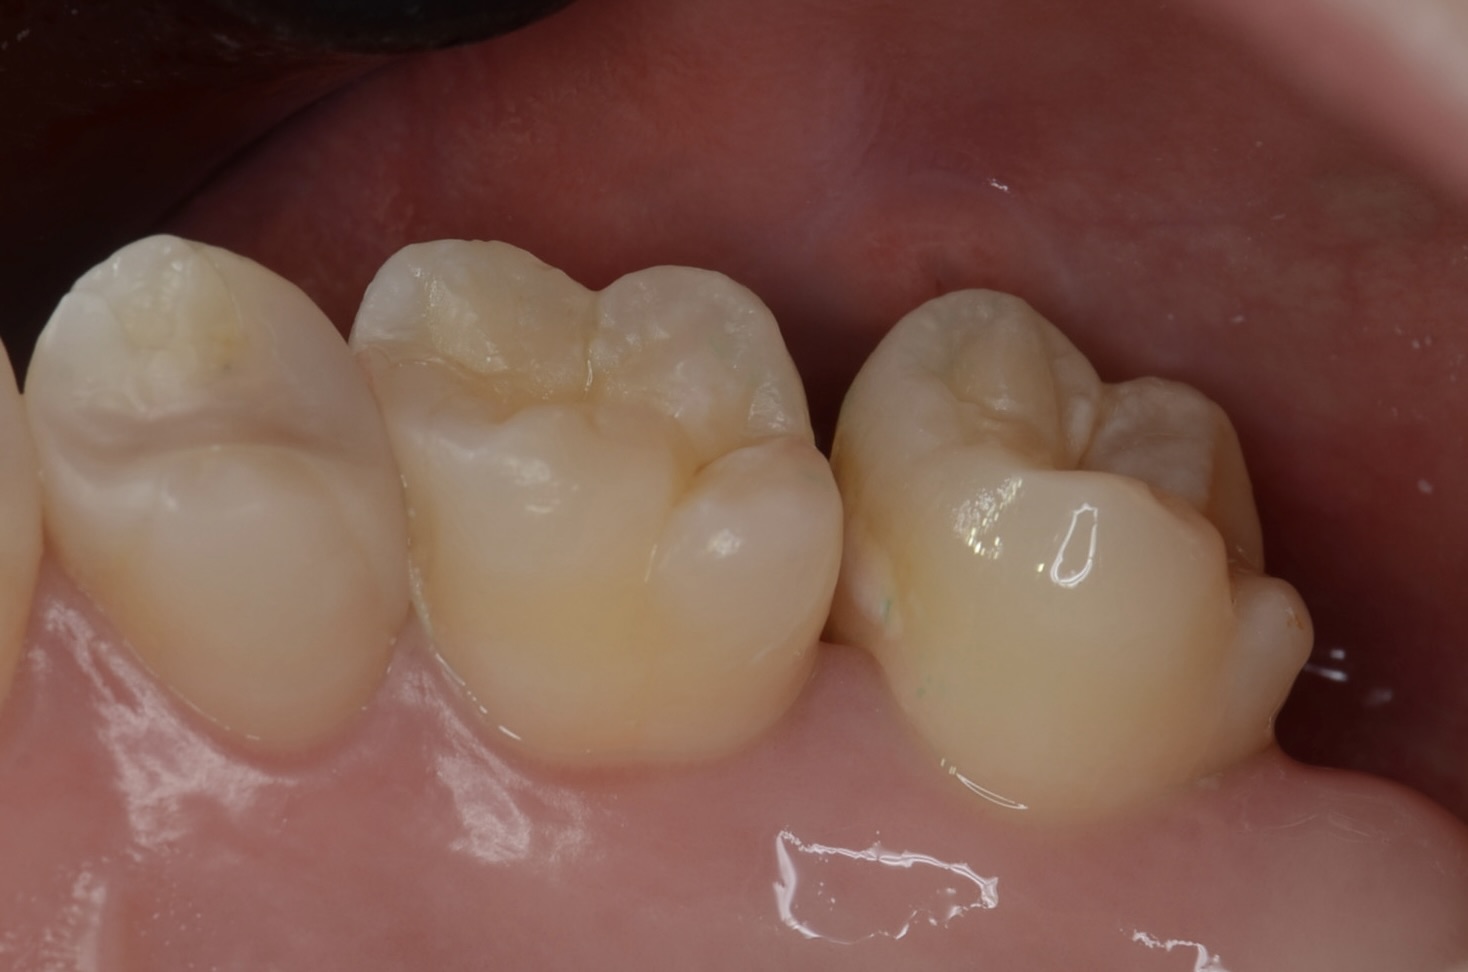

ダイレクトボンディング

フロワブルレジンの表面張力を利用して滑らかに充填します。 -

1週間後

広がった歯間が自然に閉じています。